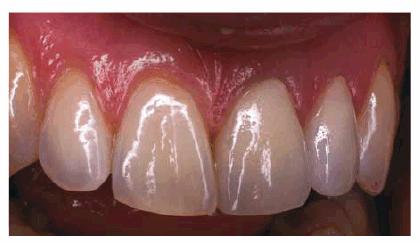

multiple referrals and consultations, but the good result (Figur 323s1823d e 18-7L) and the knowledge that

possibilities exist should be considered before a patient is allowed to lose a

tooth. The function of dentistry is to maintain the integrity of the dental

arch and to preserve the dentition. For this patient, at least, this goal was

achieved.

Figur 323s1823d e 18-7L: A total team approach was necessary to save this young lady's maxillary incisors. Both she and her parents appreciated the benefits of interdisciplinary care.